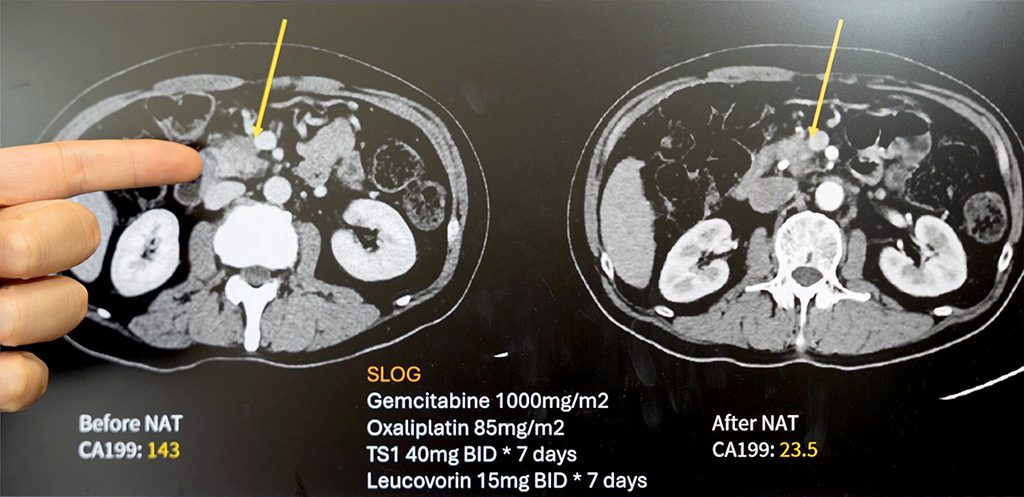

【記者吳玉惠/臺南報導】 62歲的王先生出現體重減輕與黃疸症狀,經檢查確診為胰臟癌。影像顯示腫瘤已侵犯門靜脈,屬於「邊界可切除」階段。過去此類病人往往難以直接接受手術,預後也較差。經成大醫院外科團隊多專科評估後,王先生接受「術前化學治療(Neoadjuvant Chemotherapy, NAC)」合併「擴大胰臟切除手術(Extended Pancreatectomy, EP)」。歷經四個月化療,腫瘤明顯縮小,順利完成合併血管重建的胰十二指腸切除術。術後追蹤兩年,病人恢復良好、生活如常。

成大醫院一般外科廖亭凱醫師指出,胰臟癌是極具挑戰性的惡性腫瘤之一,多數病人確診時已屬局部晚期或轉移期,無法直接手術。在沈延盛教授領導下,成大團隊積極導入「術前化療」結合「擴大切除」的整合治療策略,讓原本無法手術的病人有更多機會,也明顯延長整體存活期。

廖亭凱醫師分析成大醫院2011至2022年間共405位接受胰臟癌手術的病人,並分為早期(2011-2017)與後期(2018-2022)兩個時期比較。研究結果顯示,術前化療使用率由22%提高至75%,擴大切除手術比例也由31%上升至58%,成功讓更多晚期病人轉化為可切除族群。整體中位存活期由19.2個月延長至30.3個月,死亡風險下降49%,疾病惡化風險則降低37%。此外,擴大切除的手術死亡率也由10.4%降至2.1%,突顯團隊在高難度手術與照護方面的成熟經驗。